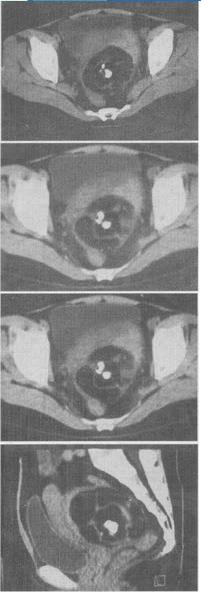

女,52岁,下腹部胀痛,B超提示盆腔占位,CT扫描如图所示,盆腔内见囊实性肿块,其内CT值不均,从—120至300Hu不等,最可能的诊断是()。

A、盆腔畸胎瘤

B、盆腔结核

C、子宫肌瘤

D、卵巢囊肿

E、卵巢黏液瘤

A